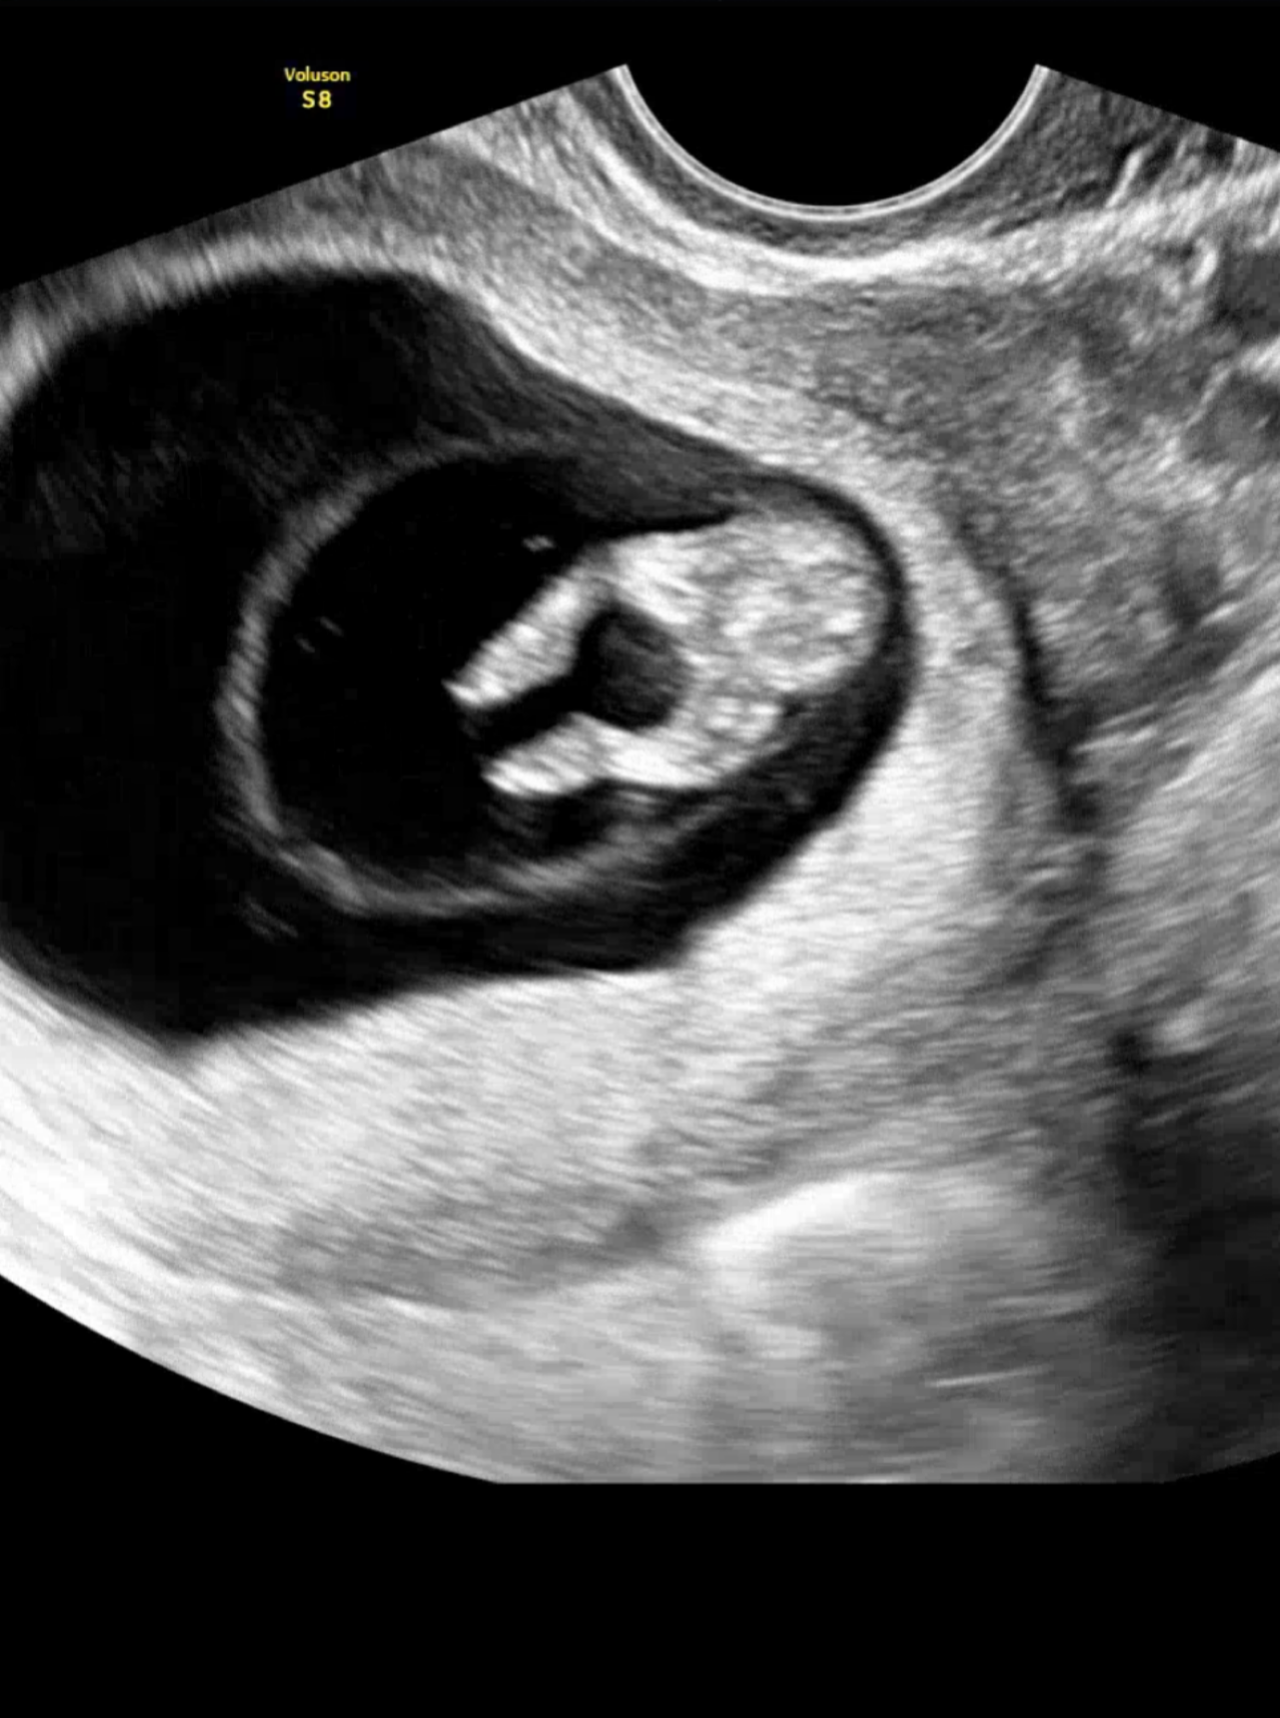

| 가슴 떨리는 임신 이야기를 공유해 주세요. | 1년 가까이 난임 치료를 이어오며 지쳤던 마음 속에서, 테스트기 두 줄이 선명하게 보였던 순간은 정말 말로 설명할 수 없는 충격과 기쁨이었어요. 늘 한 줄만 보는 것에 익숙해져 냉담해져 있던 마음이었는데, 그 자리에서 두 줄을 보니 손이 떨리고 심장이 터질 것 같았어요. 여러 번 다시 확인했는데도 같은 결과가 나왔고, 병원 혈액검사에서 ‘임신’이라는 말을 들었을 때 정말 오래 기다린 보상이 온 듯한 느낌이었습니다. |

| 치료 도중 느꼈던 가장 기뻤던 순간과 절망적인 것들은 무엇인가요? 잊지 못할 경험이 있나요? | 테스트기 한 줄이 당연하다는 듯 익숙하게 보이는 걸 자각하고는 마음이 냉담해지더라고요. 결과가 좋지 않았던 날이 많았기에 모든 게 멀게만 느껴지고, 시술을 중단해야 하나 고민도 자주 했습니다. 그런데 어느 날, 늘 한 줄만 보이던 자리에서 두 줄이 선명히 나타났을 때는 손이 덜덜 떨릴만큼 심장이 터질것 같았어요. 믿기지 않아 여러 번 확인했는데도 같은 결과가 나왔고, 내원해서 혈액검사로도 확실하게 임신이라는 소식을 듣게되었습니다. 저의 임신에 함께 진심으로 기뻐해주시고 축하해주신 이유정 원장님과 도와주신 여러 선생님들께도 말로 다 전할수 없을 정도로 감사했어요. |